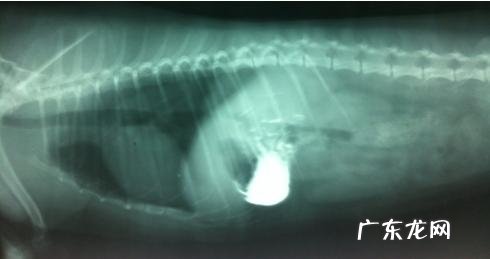

x光图

孕妇左侧睡,从x光片沒有见到异常现象 。

在孕妇左侧睡和右侧卧均沒有看得出出现异常的状况下,提议主人家灌服钡餐